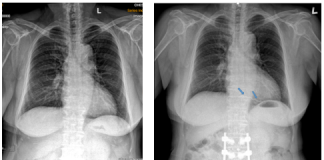

Xử trí dị vật buồng tim: Nhân một trường hợp lâm...

BS.CK2 HUỲNH THANH KIỀU(*)

BS.CK1 PHẠM PHONG LUÂN(*)

PGS.TS. BS PHẠM NGUYỄN VINH(*)

THS. BS. TRẦN THÚC KHANG(*)

BS. NGUYỄN THỊ NGỌC HÂN(**)

(*) Trung tâm Tim mạch, BV Tâm Anh TP. HCM

(**) TT Chẩn đoán hình ảnh, BV Tâm Anh TP. HCM